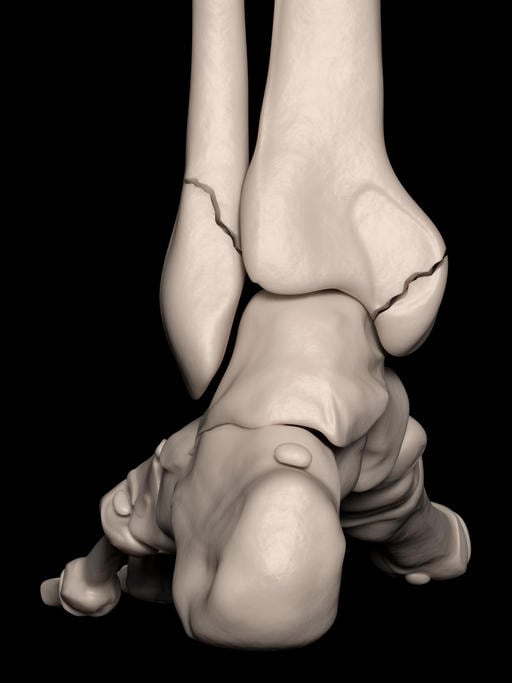

Articolazione della caviglia: cenni anatomici

L’articolazione della caviglia vede contrapporsi le estremità distali delle ossa della gamba e l’astragalo (o talo) che fa parte delle ossa piede.

Lo scheletro della gamba è composto dalla tibia, che si trova più medialmente, e dal perone (o fibula), più laterale. Tibia e perone nella loro parte distale presentano due prominenze ossee che sono visibili ai due lati della caviglia: il malleolo tibiale (o malleolo mediale) e il malleolo peroneale (o malleolo laterale).

Esiste anche un terzo malleolo, che viene detto posteriore: è costituito dalla protuberanza della parte posteriore e distale della tibia e può essere anch’esso coinvolto in una frattura della caviglia.